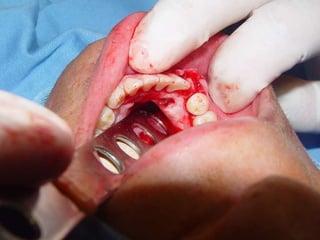

Aspecto Histopatológico Fonte Allan Giovanini Lâmina 1

Aspecto Histopatológico FonteAllan Giovanini Lâmina 1